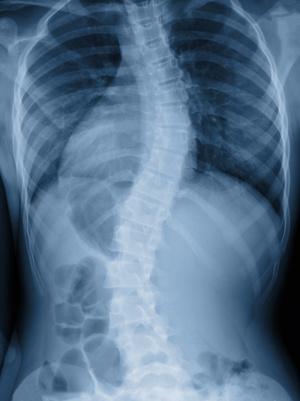

Une scoliose est une déformation permanente de la colonne vertébrale en trois dimensions. Cette déviation est due à une torsion des vertèbres survenant généralement dans l’enfance et s'amplifiant à la puberté.

Lorsqu’une déviation scoliotique est importante (au dessus de 25/28 degrés), la mise en place d’un corset de maintien pendant l’adolescence (croissance du rachis) est conseillée, associée à la kinésithérapie et à l'ostéopathie.

Il est aussi proposé, dans les grosses déviations pouvant toucher par la suite les organes internes, la chirurgie en fixant des tiges dans le dos, redressant et fixant mécaniquement la scoliose. Dans ces cas, les articulations au dessus et en dessous de la fixation doivent être surveillées attentivement pour contrôler si les contraintes qu’absorbaient la scoliose ne se répercutent pas.